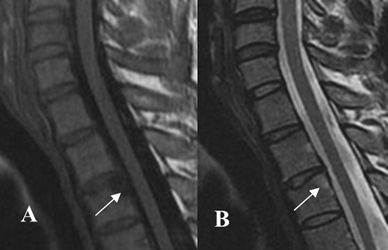

Fig 59 B. Lesiones Romanus.

A: RM sagital en T1 y B: RM sagital en T2. Lesión en la esquina posterior del cuerpo vertebral cervical, hipointenso en T1 e hiperintenso en T2, por lesión Romanus de evolución aguda.

Fig 59 C. Lesiones Romanus.

A: RM sagital en T1 y B: RM sagital en T2. Lesiones en las esquinas de las vértebras hipointensas en T1 e hiperintensas en T2, por lesiones Romanus de evolución aguda. Hay otras lesiones hiperintensas en ambas secuencias, por evolución subaguda.